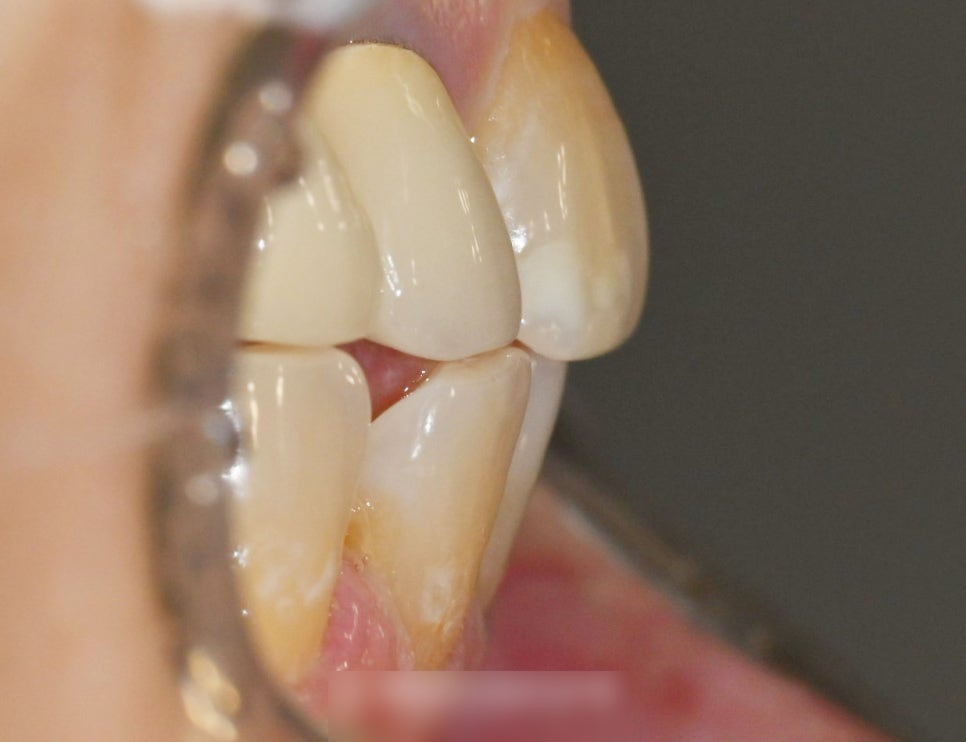

이와 같이 아래 앞니 사이 벌어짐은

말할 때, 밥 먹을 때 잘 보입니다.

살짝 다문다 하더라도

이와 같이 형성된 공간을 찾을 수 있습니다.

간격이 어느 정도 있는 편이라

눈에 크게 띌 수밖에 없는데요.

전반적으로 봤을 때,

전체 교합은 괜찮습니다.

부분교정을 통해 개선해볼 수 있습니다.